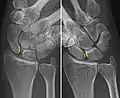

A dynamic scapholunate instability is where the scapholunate ligament is completely ruptured, but secondary scaphoid stabilizers are still preserved;[6] these are the scaphotrapezial (ST), scaphocapitate (SC) and radioscaphocapitate (RSC) ligaments.[6] In a static scapholunate instability, these other ligaments are ruptured as well.

X-ray images indicate scapholunate ligament instability when the scapholunate distance is more than 3 mm, which is called scapholunate dissociation.[7] A static scapholunate instability is generally readily visible, but a dynamic scapholunate instability can only be seen radiographically in certain wrist positions or under certain loading conditions, such as when clenching the wrist, or loading the wrist in ulnar deviation.[6]

Dynamic instability: Increased scapholunate distance (between yellow lines) upon ulnar deviation of the wrist, but not otherwise.